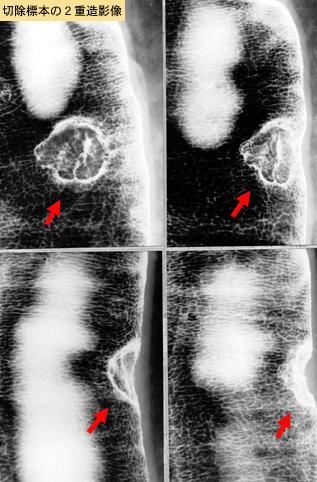

疾患(病理主体)の分類悪性上皮性腫瘍/腺癌

部位(臓器別)大腸/S状

検査方法X-P

腫瘍の肉眼分類2型(潰瘍限局型)/

病変の最大径(ミリ)10〜14

腫瘍の深達度mp